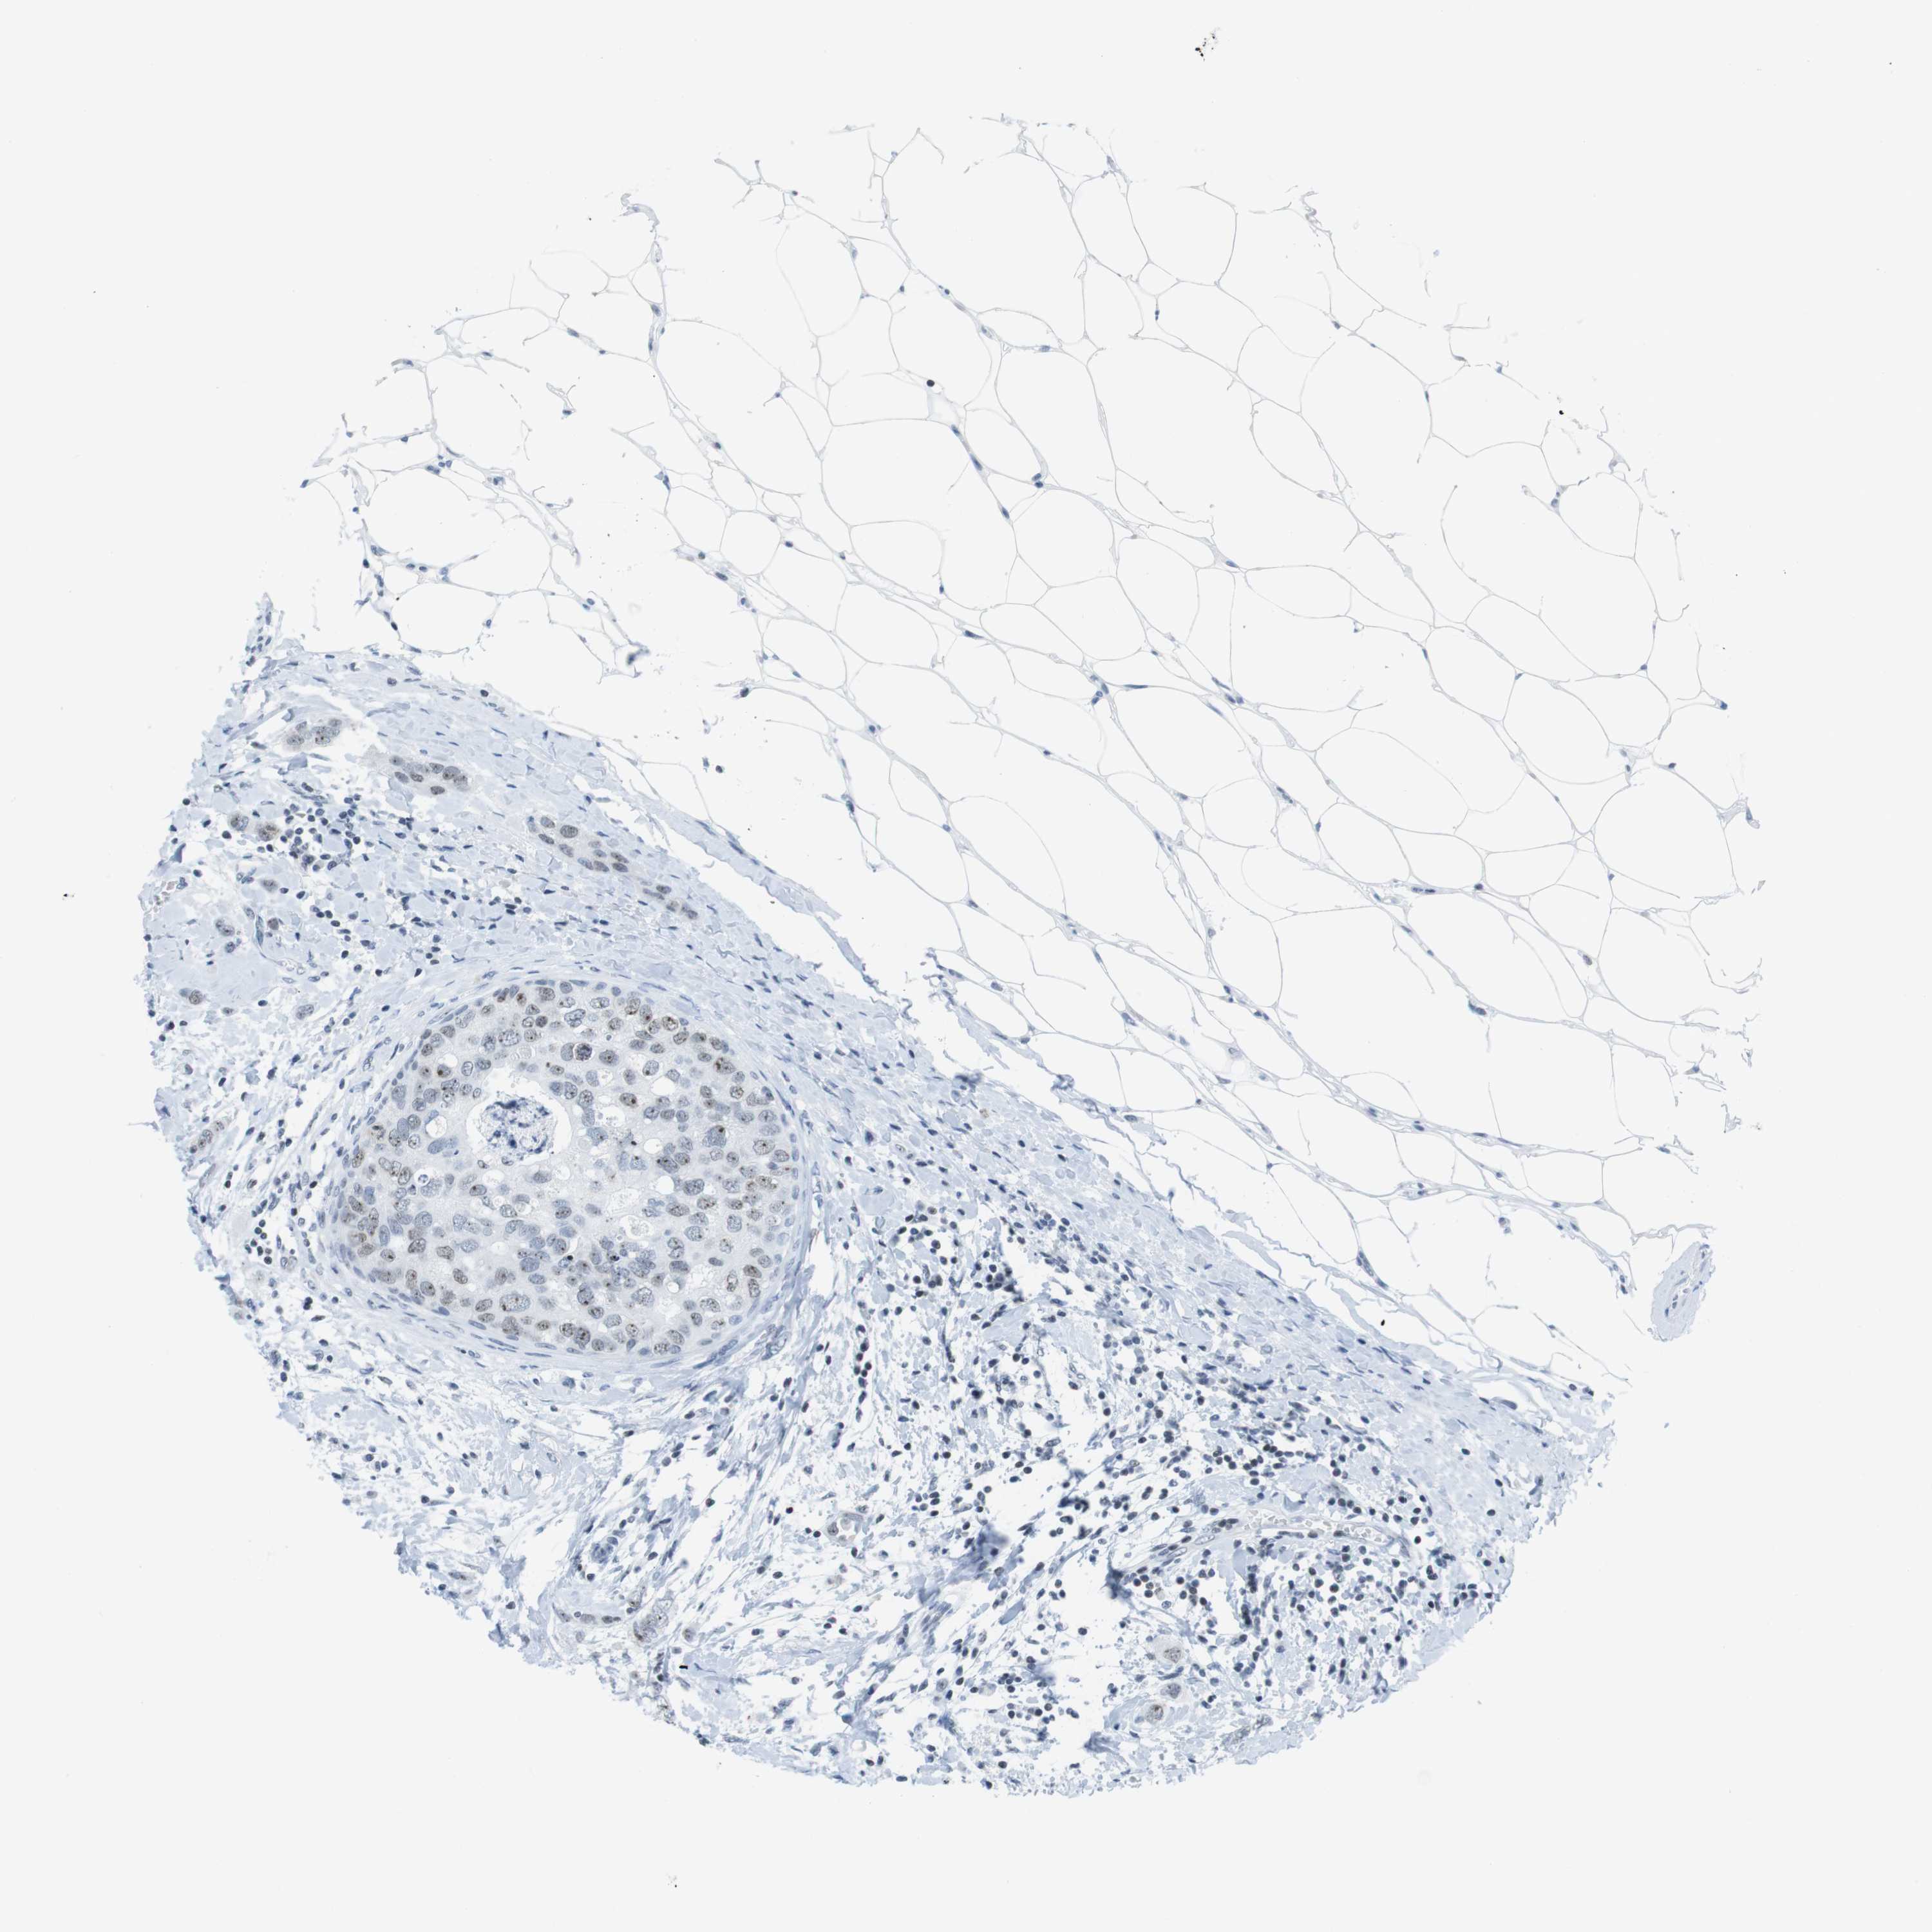

CANCER BREAST CANCER Show tissue menu

BRCA TCGA BRCA VALIDATION PROTEIN EXPRESSION

Breast cancer

Human cancer